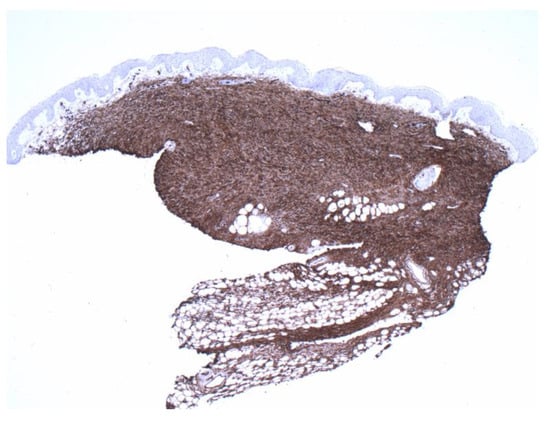

Figure 4.

Positive CD34 staining with contrasting sparse-superficial and dense-deeper areas (4×).